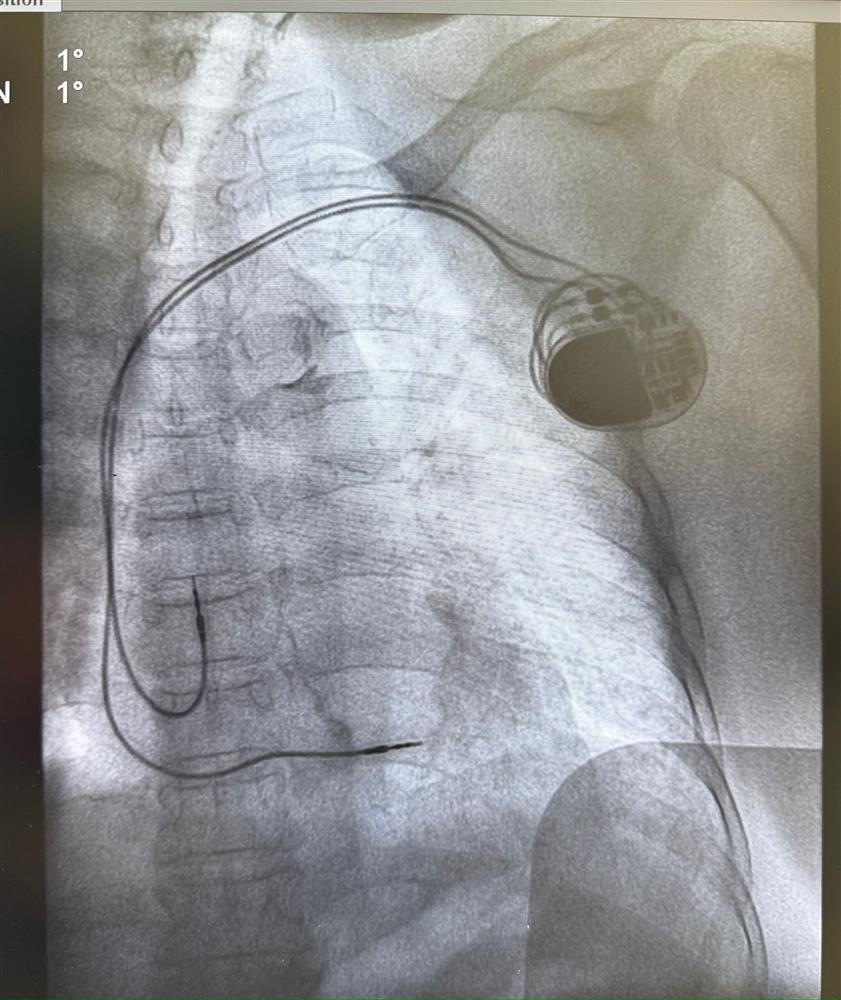

Hình 2: Hình ảnh đặt máy tạo nhịp vĩnh viễn thành công

Kỹ thuật đặt máy tạo nhịp vĩnh viễn được thực hiện trong phòng can thiệp mạch (DSA) với sự chính xác tuyệt đối. Các bác sĩ đã đưa dây điện cực qua tĩnh mạch dưới dòn bên trái vào buồng tim và đặt máy tạo nhịp dưới da vùng ngực trái. Sau gần 1 giờ thực hiện, máy tạo nhịp hoạt động ổn định, kiểm soát nhịp tim của bệnh nhân.